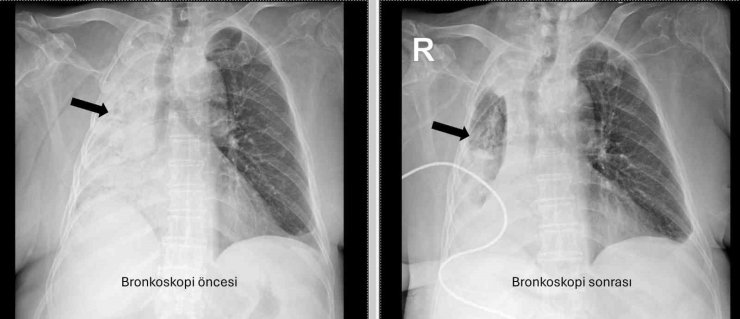

Denizli'de yaşayan ve emekli öğretmen olan 78 yaşındaki felçli kadın son zamanlarda sık sık akciğer enfeksiyonu nedeniyle hastaneye gidiyordu. 1 ay önce gittiği hastanede bronkoskopi yapılmasına rağmen sorun saptanmadığı öğrenildi. Yaşlı kadının son gittiği hastanede sağ akciğerinin tamamen kapandığının tespit edilmesi üzerine Pamukkale Üniversitesi Hastanesine başvuruldu. PAÜ Hastaneleri Göğüs Hastalıkları Anabilim Dalı Öğr. Üyesi Prof. Dr. Göksel Altınışık Ergur, tarafından yapılan tetkiklerde sağ akciğere giden hava yolunun bütünüyle kapalı olduğu görüldü. hastaya acil bronkoskopi planlanıp hemen işlemin gerçekleştirildiğini söyleyen Prof. Dr. Altınışık Ergur, "Fleksibl (esnek, eğilip bükülebilir) bronkoskop ile hava yolları incelenirken çok yoğun ve koyu sekresyon olduğu, bunun iyice temizlenmesi sonucunda ancak hava yollarının incelenebileceği görüldü. Aspiratör (içerideki salgıları emmeye yarayan bir cihaz) sayesinde hava yollarına steril sıvı verilip emilerek bu temizlik yapıldı. Sonrasında sağ akciğere giden hava yolunda sarı bir nesne olduğu görüldü. Bu hâliyle yabancı cisim olduğu anlaşıldığı gibi bunun mısır tanesine benzerliği de açıktı. Yabancı cismi çıkarma işlemi genel anestezi altında, rijit bronkoskop ile yapılmak üzere planlanabilirdi; çünkü bu durumun tedavisi yabancı cismin oradan, ek sorun oluşturmaksızın çıkarmaktı. Ancak, genel anestezi altındaki bir işlem için hastanın genel durumu bozuk olduğundan, özellikle ek hastalıkları ve enfeksiyon varlığı ile işlem riski artacağından hastadaki cismin fark edildiği sırada çıkarılmasına şans vermek daha uygun görüldü. Hava yolu içindeki sıvıları emen aspiratörün gücünü kullanılarak cismin çıkarılması mümkündü. Bronkoskobun ucu, sarı cismin gövdesine dayanıp aspiratör ile emme sayesinde ikisi birbirine sımsıkı yapıştırıldı. Emme gücünün azaltılmamasına dikkat ederek yabancı cisim ve bronkoskop, aynı zamanda hava yollarından dışarıya başarı ile çıkarıldı. İşlem sonrasında hasta yakınına mısır tanesi açısından tıbbi öykü yeniden sorulduğunda, hastamızın bundan beş ay önce yediği pizzanın üzerinde mısır taneleri olduğu öğrenildi. O sırada ani bir yakınma ortaya çıkmadığı için böyle bir ihtimal akla gelmemişti. Düşkün hastalar taneli gıdalar yerken, bu durumun fark edilmeden de gelişebileceğini göstermesi açısından önemli olan bu tablo, hastaların bir dedektif titizliği ile değerlendirilmesi gerekliliğini bir kez daha ortaya koymaktadır" dedi.